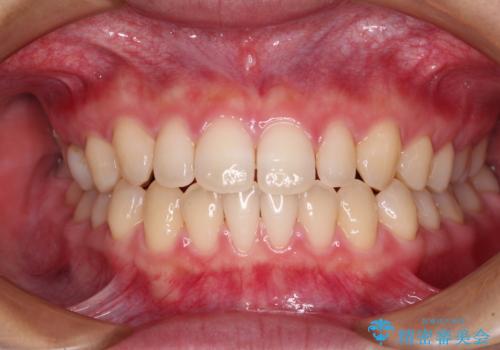

隙間だらけの歯列 インビザラインで改善

舌癖を改善するためのトレーニングを行いながら、インビザラインにより上下の前歯の隙間を閉じていくこととしました。

空隙歯列(すきっ歯)は、舌の突出癖をある程度改善できたとしても、後戻りにより隙間が開きやすいと言われています。

裏側から細いワイヤーで保定するとともに、睡眠時のマウスピース装着を徹底していただくことで、後戻りを最小限にとどめます。